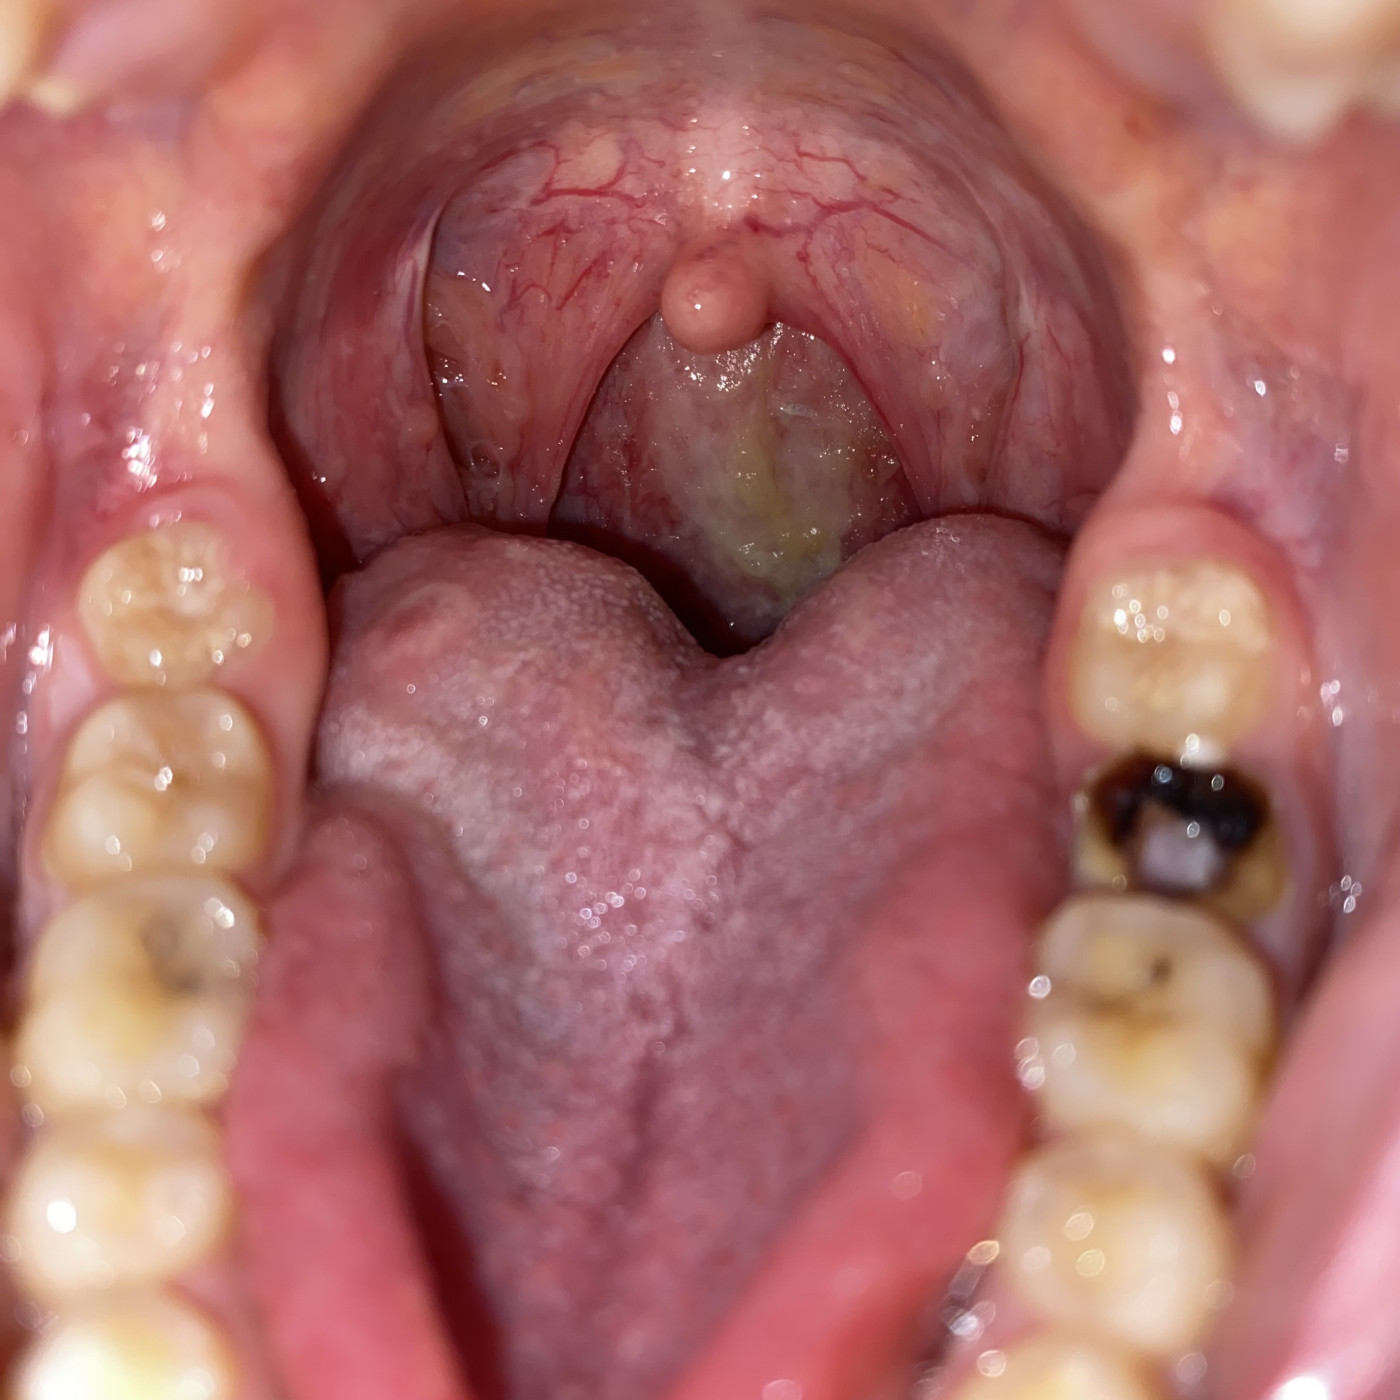

Что у меня на гортани !   1 ответ

Был гнойный мешочек , после недолгого лечения остались по гортани гнойные потеки и черное образования